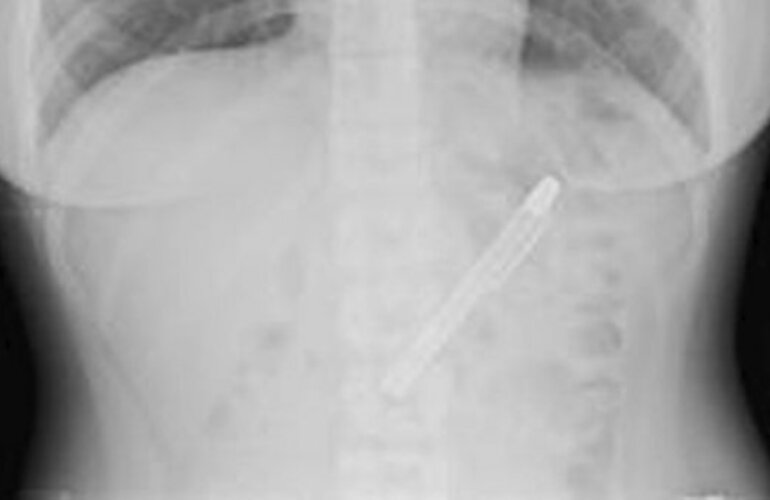

Fue al hospital, le hicieron una radiografía y encontraron el objeto que estaba ahí hace nada menos que seis meses.

Taiwán.- Tenía un dolor terrible en la panza que no la dejaba comer y, como no podía aguantar más y el dolor continuaba, decidió ir al hospital. Después de hacerle una serie de pruebas se toparon con una pluma estilográfica, que estaba ahí desde hacía nada menos que seis meses.

La radiografía que le hicieron en el hospital de Taipei, en Taiwán, no dejaban dudas que la lapicera estaba ahí y la estudiante no tenía la menor idea de cómo había llegado ahí. Según comentó, puede que la introdujera en su organismo el día que celebró la fiesta de fin de exámenes en la que se pasó de copas.